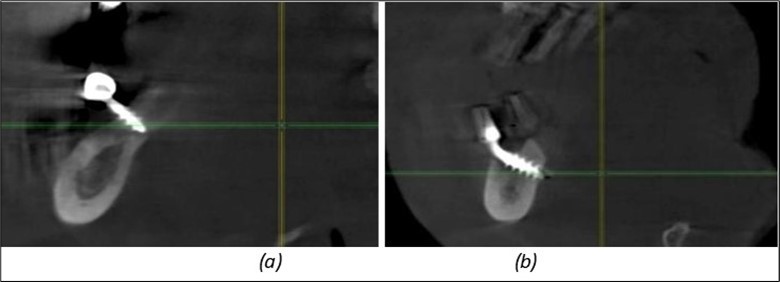

A total of 11 implants is placed in the maxilla, including compressive TPG implants with a polished surface in the maxillary-sphenoid fusion area (Figure 3, Figure 9). Similarly, in the anterior region, final fixation is achieved in the nasal cortex, and BCS corticobasal implants are added in areas with massive bone loss in the frontal region (Figure 3, Figure 8, Figure 11). Additionally, in the palatal sinus cortical area, with the aim of avoiding the addition and sinus lift zone where the second cortical bone no longer exists, 3 implants are placed, 2 in quadrant 1 and 1 in quadrant 2 (Figure 3, Figure 8). Through the Caldwell-Luc sinus lift procedure, the sinus cortical bone is displaced to allow the placement of the graft material and elevation of the sinus membrane. This sinus cortical is no longer recreated at the junction of the graft material and mucosa-sinus membrane, making it impossible to place a corticobasal implant, which relies on the second cortical bone. In the distal mandibular area, after the removal of two stage implants due to massive destruction in quadrant 3, implant placement distal to the mylohyoid line is not possible, as in quadrant 4 (Figure 10). A re-intervention occurs after 5 months to stabilize the area (Figure 12, Figure 14). Also, at the moment of fixation, the tip of one implant fractures, and the decision is made to leave it in place due to regional bone destruction, in order to avoid enlarging the bone defect.

Figure 12.Implants fixed distally in quadrant 4 with fixation at the level of the mylohyoid line: (a) The most distal implant fixed in unaffected bone from the previous restoration; (b) The implant fixed in the area where the two stage implant was removed.